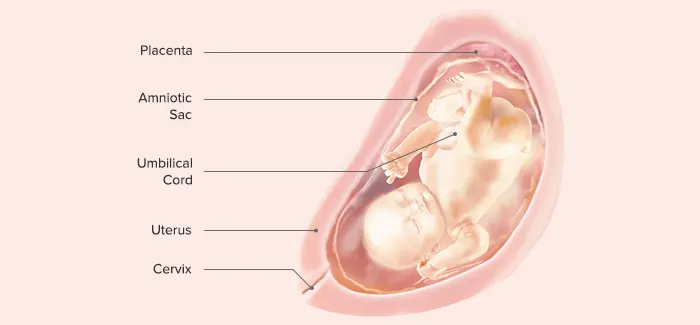

VIII. End of 32nd Gestational Week

Length: 38–43 cm

Weight: 1600 g

Subcutaneous fat begins to be deposited (the former stringy, “little old man” appearance is lost)

The fetus responds by movement to sounds outside the mother’s body.

Active Moro reflex is present.

Iron stores, which provide iron for the time during which the neonate will ingest only milk after birth, are beginning to be developed.

Fingernails grow to reach the end of fingertips.

IX. End of 36th Gestational Week

Length: 42–48 cm

Weight: 1800–2700 g (5–6 lb)

Body stores of glycogen, iron, carbohydrate, and calcium are deposited.

Additional amounts of subcutaneous fat are deposited.

The sole of the foot has only one or two crisscross creases, compared with the full crisscross pattern that will be evident at term.

The amount of lanugo begins to diminish.

Most babies turn into a vertex (head down) presentation during this month.